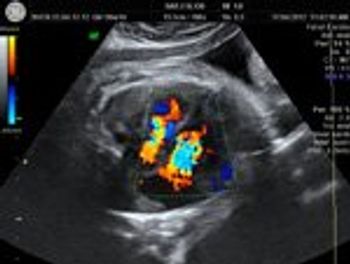

These are ultrasound images of an early pregnancy.

Our patient presented at 29 weeks gestation for a routine prenatal ultrasound.

What is your diagnosis of this 36 week old fetus with cardiomegaly?